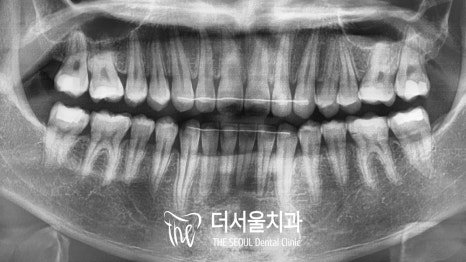

이제 아랫니가 많이 보입니다.

올바른 피개량을 갖게 되어

이전에 비해 훨씬 편안하고

안정적인 모습으로 바뀌었습니다.

절단연부터 느껴지는 비대칭도

상당 부분 나아진 것을 볼 수 있으며

정중선도 알맞게 일치하고 있네요.

구치부 교합도 훨씬 긴밀해졌으며

톱니바퀴와 같이 잘 물리고 있는 모습입니다.

전체적으로 정상 교합으로 바뀌었는데요.

교합면에서 관찰해보면

밖으로 뻗쳐 있던 어금니들도

제 위치를 찾아 돌아온 것을 볼 수 있네요.